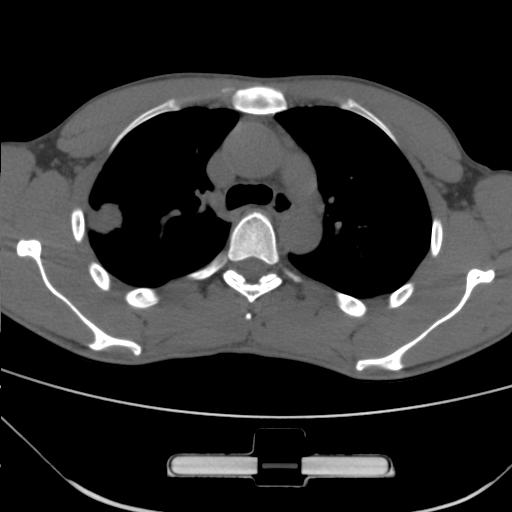

车祸伤者

右肺上叶后段近胸膜下结节样异常密度灶,似见分页及毛刺,考虑右肺上叶周围型肺ca,建议穿刺病理检查

缺乏病史,症状体征,但这个孤立结节具备了几乎所有的恶性征象:分叶,毛刺,空泡征,胸膜凹陷征,血管集束。